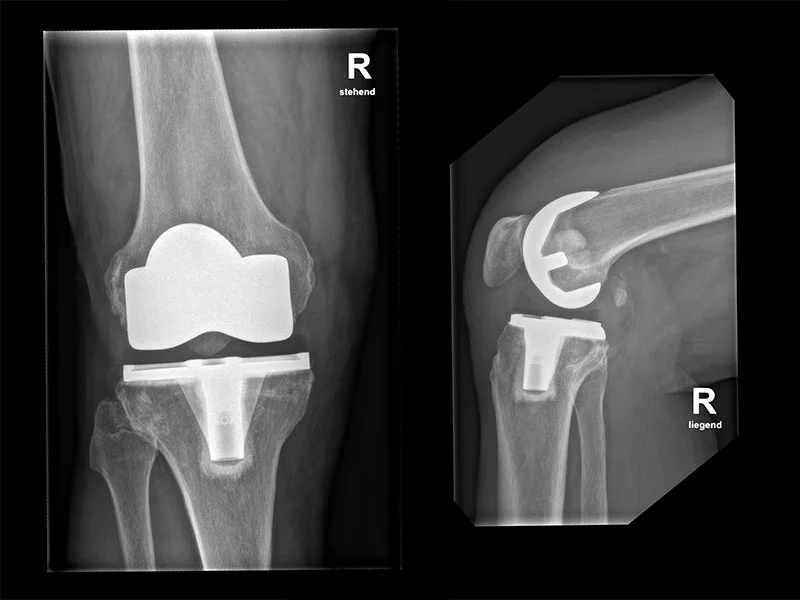

Operative Therapie

Wenn nicht-operative Behandlungen keine ausreichende Linderung bieten, kann eine Operation erforderlich sein. Zu den gängigen operativen Verfahren gehört v.a. die Kniegelenksprothese. In manchen Fällen, z.B. bei ausgeprägtem O- oder X-Bein, kann eine Begradigung der Beinachse («Umstellungs-Osteotomie») zur Anwendung kommen.

Die Auswahl der geeigneten Operationstechnik hängt von verschiedenen Faktoren wie dem Grad der Arthrose, der Anatomie des Patienten und den individuellen Bedürfnissen ab. Neben der oben erwähnten Begradigung der Beinachse gehören die Teilprothese und die Totalendoprothese zu den gängigen Operations-Techniken.